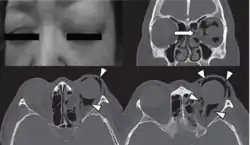

| Woman with preorbital swelling in orbital emphysema shown in CT scans | |